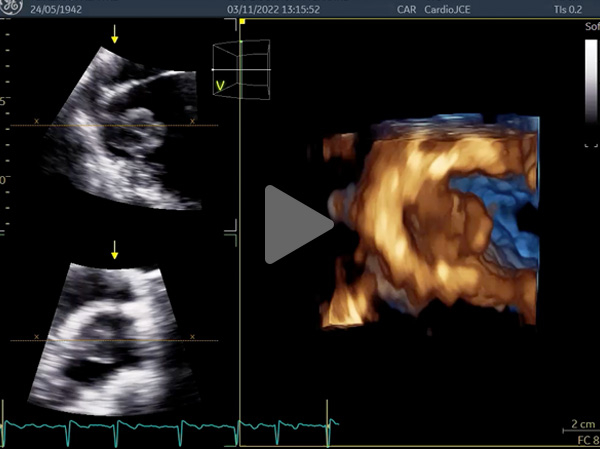

Vidéos 5 à 7 et figure 9 : Masse arrondie de 43 mm de diamètre flottant librement dans l’oreillette gauche avec enclavement périodique dans l’orifice mitral : « ball thrombus »

Vidéo 5

Vidéo 6

Vidéo 7

Figure 8

Figure 9 : ball thrombus

Figure 10 : thrombus auricule